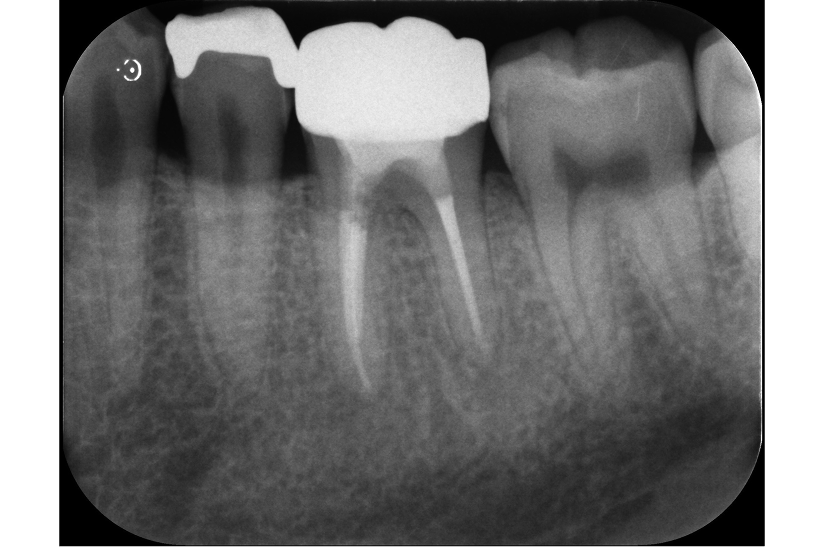

再根管治療で奥歯を残した症例

タップで写真の拡大ができます。

Before

After

主訴

噛むと違和感がある。

治療内容

リトリートメント(再根管治療・大臼歯)

ファイバーポストコア

治療期間

1ヶ月

治療費用

198,000

治療の

リスク

根尖部透過像が完全に消失しない可能性があります。